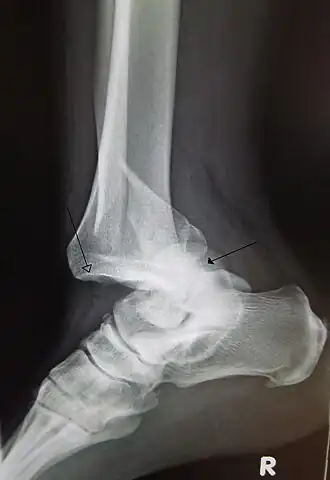

Description de cette image, également commentée ci-après

Une luxation traumatique de l'articulation tibio-talaire de la cheville avec une fracture fibulaire distale. La flèche creuse montre le tibia et la flèche pleine le talus.

Luxation de la cheville et du pied